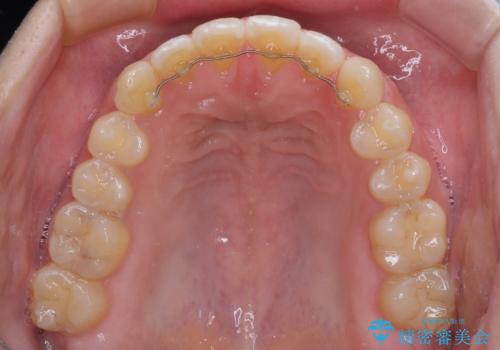

【モニター】隙間だらけの前歯を治したい インビザラインによる矯正治療

- 上下前歯の隙間と咬み合わない前歯を気にして来院された患者様です。

開咬の治療は、前歯を閉じるように動かすとともに、上下臼歯を圧下(骨内にめり込ませる)させることで進めて行きます。

インビザラインは臼歯の圧下を効果的に行えるため、インビザラインを用いて矯正治療を行うこととしました。

開咬とすきっ歯は、舌の突出癖改善が必須となるため、トレーニングを徹底的に行うよう指示しました。